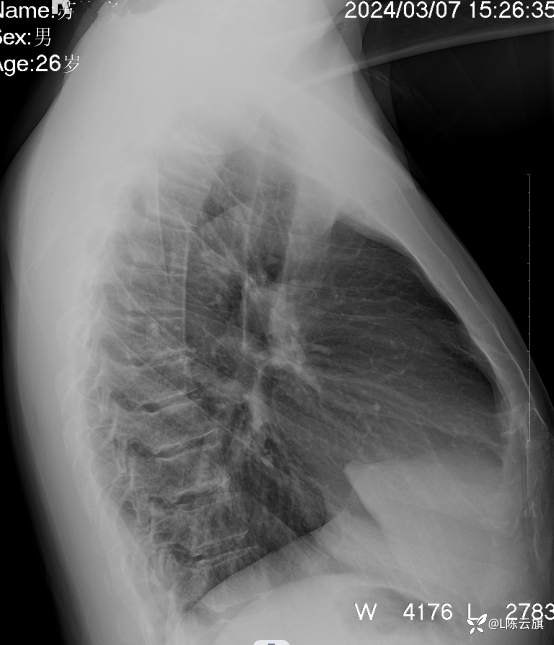

1、患者男,26岁,精神病住院患者。没有胸部及呼吸系统症状。正侧位胸片考虑什么?第一 次拟肺炎治疗后复查无改变!

2、平片所见:(CT随后上传!)